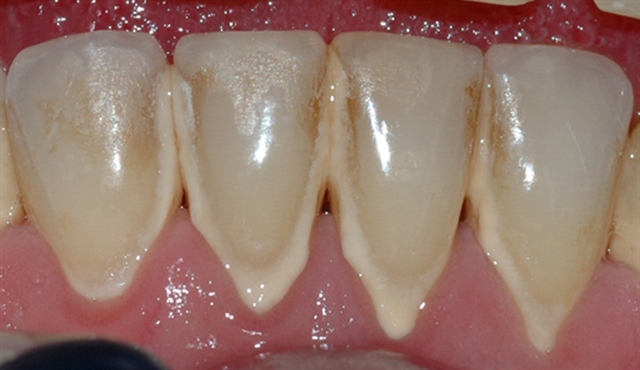

• Biletet viser eit tannsett med synleg tannstein og misfarging.

• Biletet viser eit nærbilete av tennene i underkjeven med tannstein og misfarging.

• Biletet viser tilhøva i underkjeven etter at tannstein og misfarging er fjerna.